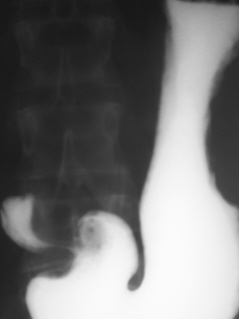

При полипозиционном исследовании луковицы 12-ти перстной кишки с дозированной компрессией «мягким дистинктером» в области препилорической части выявлен одиночный полип до 0,5 см. в диаметре, не правильной округлой формы. Отдельные мелкие дефекты наполнения в области луковицы «со скоплением» их в области кармана по малой кривизне – иллюстрации 5, 6.

На иллюстрации 7 показано «отображение» полипоподобных образований в области кармана по большой кривизне после цифровой обработки.

Значит я тоже видел полип... В луковице ДПК округлый дефект наполнения на ножке на верхне - медиальной стенке, около 1 см в диаметре, не изменяющийся при прохождении перистальтической волны.